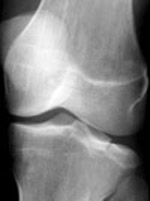

| AP and lateral knee views of a subtle fracture. | ||||||